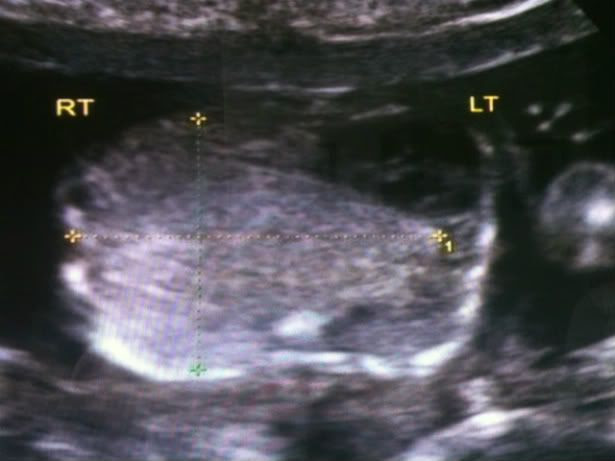

At our 20 week ultrasound they found a complication with our lil' guy.

He has a growth, known as a CCAM, on the outside of his right lung. It sits in between his lung and the ribcage.

To find out more details of what we are looking at, they sent us to the MFM of Utah at St. Marks. There we were able to get a better view of the growth and they were able to give us some scenarios for the upcoming future.

Basically there are three ways for the CCAM to develop:

a. (promising and what we are all hoping for) Around 28 weeks the growth will cease to continue to grow along with him and will stay as it is until birth. After birth we would meet with a pediatric surgeon and schedule a time for it to be removed.

b. (not a good as the first but manageable) It will continue to grow at the same rate as he is, without any fluid building up around the abdomen, heart and lungs. After birth the growth will be removed so the right lung will be able to continue developing and so it will not inhibit his breathing.

c. (trying not to think about it) It will grow at a faster rate or fluid will develop putting stress on his organs, mainly his heart, and send him into heart failure. There are two options for this: they can go in and put a shunt in and drain the fluid, however it will leave pockets that will eventually fill again. second there is an in-utero surgery that can be preformed to remove the growth. Both come with high risks and lower survival rates. Both options tend to start pre-term labor and if it cannot be stopped then the baby is delivered. Both of these options usually take place around the 28 week mark so you can see the risks there.